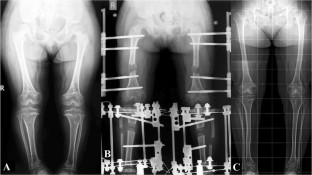

Fig. 1